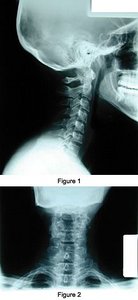

Limited cervical studies (AP and lateral) were obtained at this facility at time of history and physical. Diagnostic yield includes cervical lordosis nonmaintained with alordosis, facetal sclerosis, and cervical spondylosis at C5 and C6. AP view: uncinate processes and adjacent fossae show projecting osteophytes and sclerosis. The soft-tissue structures are unremarkable and bone density is adequate. There is no evidence of any frank osteolytic or osteoblastic findings, congenital findings or obvious fractures (figures 1 and 2).